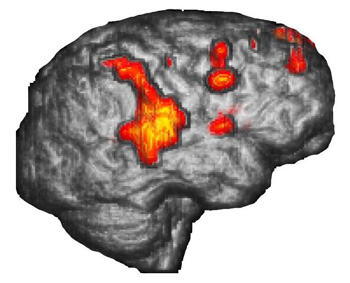

Case 1

Right hemisphere in 3D-surface rendition

Right handed 15 year-old-boy with intractable epilepsy performing a verbal "repetition task." The surface rendition beautifully depicts the activation occurring in the posterior third of the right superior temporal gyrus and extending toward supramarginal gyrus and Brodmann's area 7. The areas of activation are better displayed than with conventional 2D MR images.